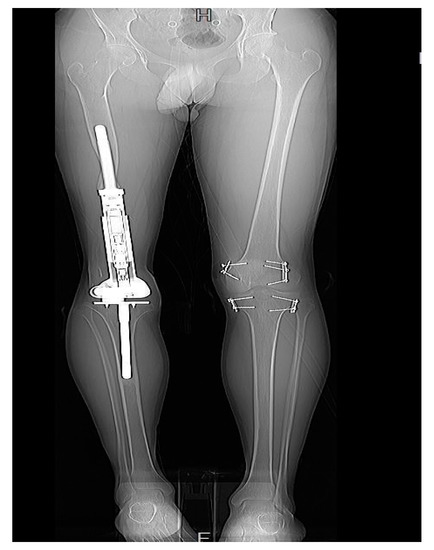

3.6. Need for Further Management

Patients with rotational and angular deformities did not necessitate management, as the deformities were tolerated well. Moreover, patients with an LLD of less than 10 mm demanded no further management. An LLD between 10 and 20 mm was managed solely by a shoe lift. However, an LLD of >20 mm, was treated on a case-by-case basis. Two patients required operative revision and serial elongation due to the anticipated growth potential of the contralateral leg. The remaining two patients were managed using epiphysiodesis of the contralateral distal femur and proximal tibia (Figure 7).

Figure 7.

Patient 3 had undergone EDFE using MUTARS® Xpand. However, due to an LLD of 37 mm, this patient required epiphysiodesis of the contralateral limb.